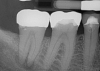

Fig 2. Final fill with the .04 taper 035 gutta-percha to the verified 29-mm working length.

Figure 2

The canal was prepared with an 035 (.04 taper) NiTi rotary file to the 29-mm working length with large amounts of water-soluble gel (Figure 2). The rotary files were supplied in lengths of 21 mm, 25 mm, and 31 mm. The system provided matching paper points and gutta-percha in all file sizes. Irrigation took place with NaOCl before the solution was allowed to remain in the canals for 30 minutes. After the irrigation, CO2 laser technology was used for 20 seconds to eliminate bacterial and viral contaminants. The laser evaporated any residual bacteria or viruses that remained after irrigation. The laser was an effective modality for root-canal sterilization.4